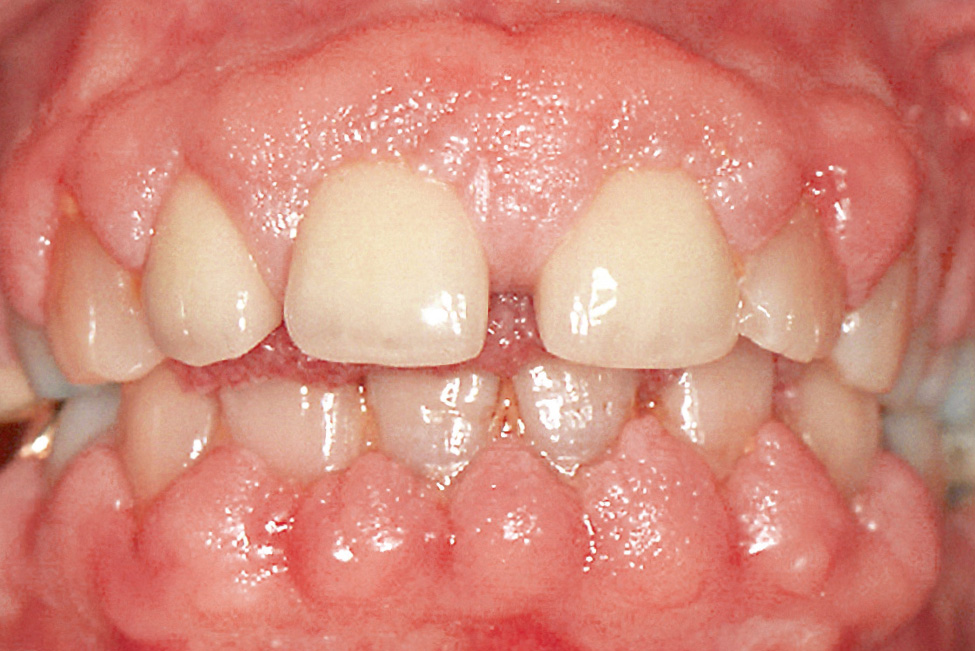

Abb. 4 Phenytoininduzierte Gingivawucherung.